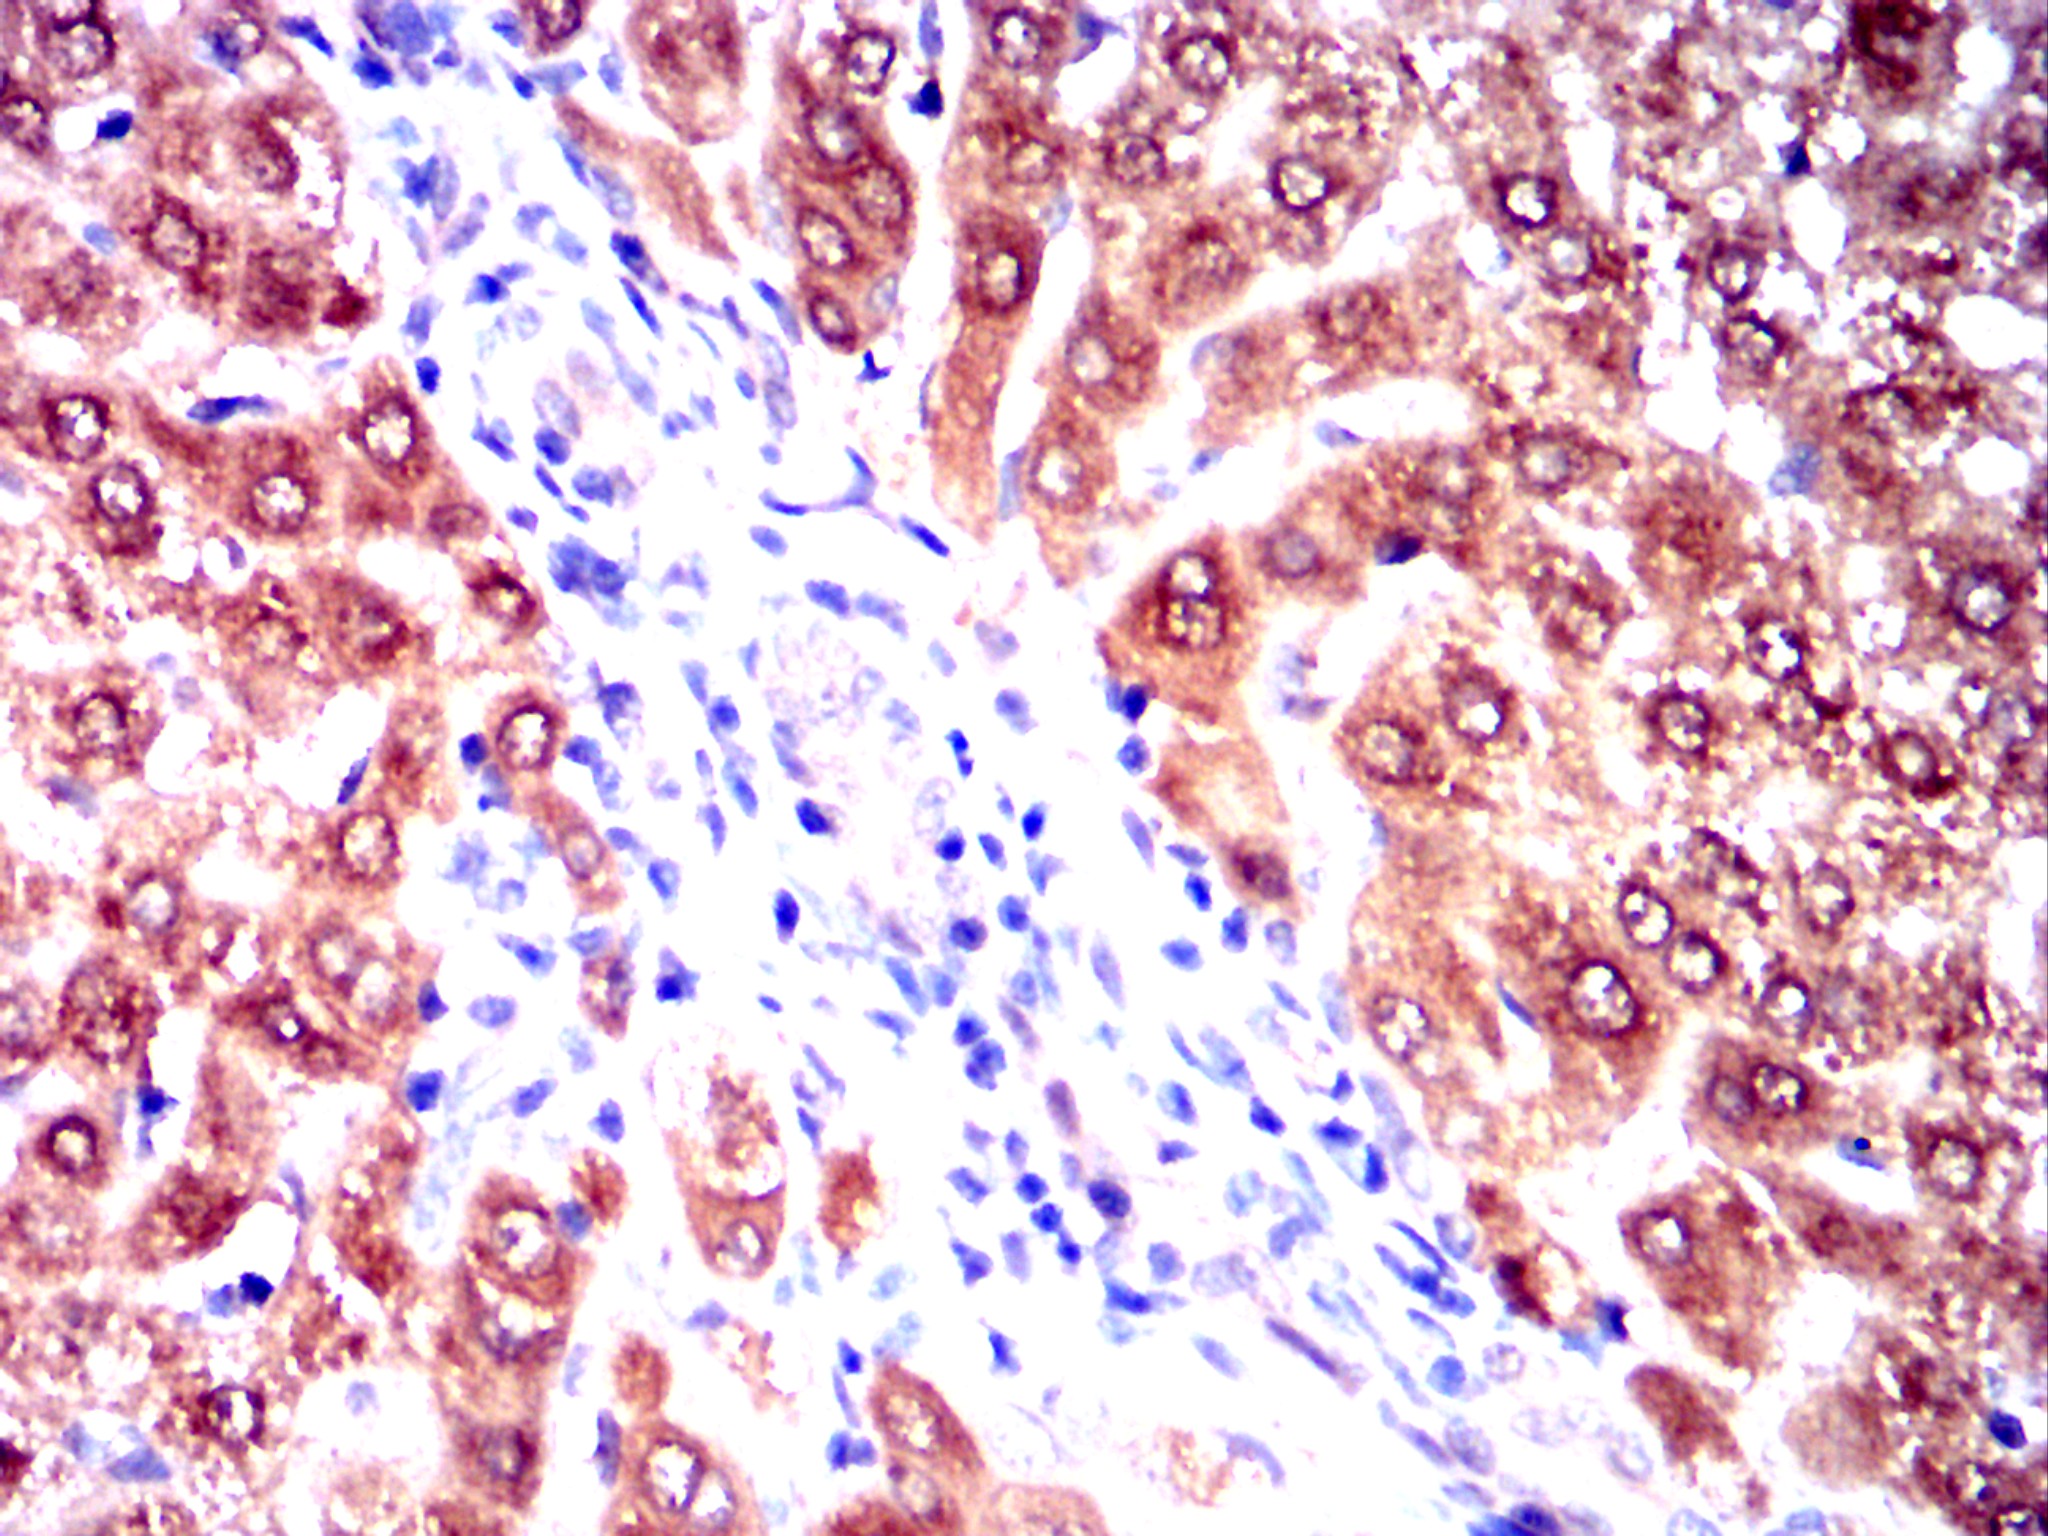

Immunohistochemical analysis of paraffin-embedded human lung cancer tissues using AKR1C1 mouse mAb with DAB staining.